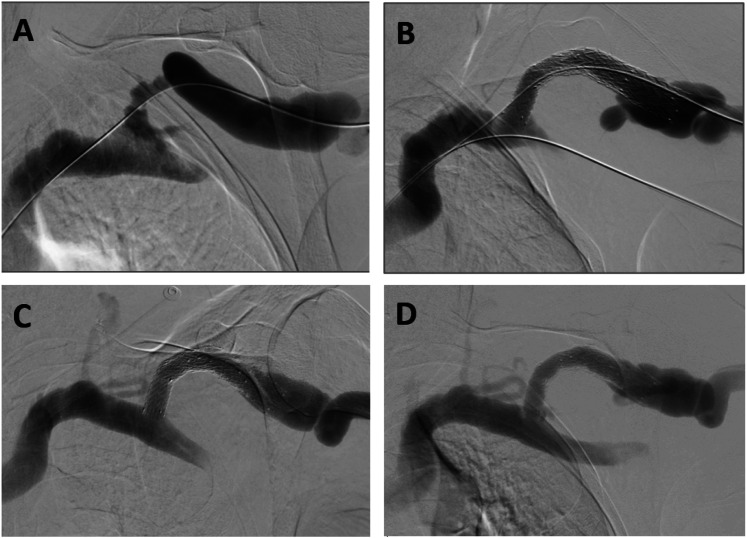

目的描述西澳大利亚一家三级医疗中心使用 WRAPSODY 细胞防渗内支架的临床效果:使用 WRAPSODY 治疗动静脉通路静脉外流顽固性闭塞疾病患者。对患者进行前瞻性随访,直至术后 12 个月。研究指标包括 30 天不良事件、技术成功率、靶病变主要通畅率、通路主要通畅率和辅助通路主要通畅率:结果:共使用 27 台 WRAPSODY 设备治疗了 15 名连续患者。技术成功率为 100%。随访期间未发现与设备相关的不良事件。两名患者未完成全部随访。3个月、6个月和12个月的靶病变主要通畅率分别为100%(15/15)、100%(15/15)和100%(13/13)。3个月、6个月和12个月时通路原发性通畅率分别为73.3%(11/15)、46.7%(7/15)和46.2%(6/13)。在 33.3%(5/15)的病例中观察到边缘狭窄,在血管造影显示通路初级通畅失败的 8 位患者中,有 5 位是边缘狭窄。12个月后,初级辅助功能通畅率为100%:结论:在现实世界中,WRAPSODY 可以安全地用于解剖结构复杂的肾脏通路狭窄病变患者,并具有持久的通畅性。与该装置相关的治疗优势可能会鼓励在临床实践中更广泛地使用该装置。

ObjectiveTo describe clinical outcomes associated with the use of the WRAPSODY Cell-Impermeable Endoprosthesis at a tertiary center in Western Australia.MethodsPatients with recalcitrant occlusive disease in the venous outflow of their arteriovenous access circuits were treated with WRAPSODY. Patients were prospectively followed up to 12-month post-procedure. Study measures included 30-day adverse events, technical success, target lesion primary patency, access circuit primary patency, and assisted access circuit primary patency.ResultsTwenty-seven WRAPSODY devices were used to treat 15 consecutive patients. The technical success rate was 100%. No device-related adverse events were observed during the follow-up period. Two patients did not complete the full follow up. Patency rates at 3-, 6-, and 12 months for target lesion primary patency were 100% (15/15), 100% (15/15), and 100% (13/13), respectively. Rates for access circuit primary patency at 3-, 6-, and 12 months were 73.3% (11/15), 46.7 % (7/15), and 46.2% (6/13), respectively. Edge stenosis was observed in 33.3% (5/15) of cases and accounted for 5 of the 8 patients who experienced failed access circuit primary patency on angiogram. Primary assisted functional patency was 100% at 12 months.ConclusionWRAPSODY can be utilized safely and has durable patency in real-world patients with complex anatomical renal access stenotic lesions. The therapeutic benefits associated with the device may encourage broader use in clinical practice.